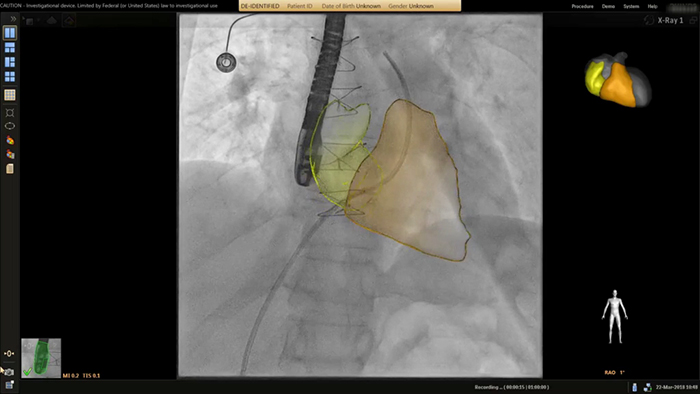

Anatomical landing zone marking on TSM Pro

SmartCT live guidance

Aortic coarctation stenting guidance with VesselNavigator